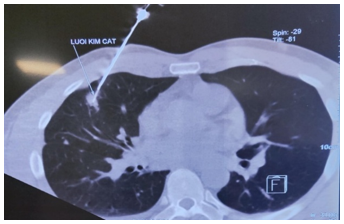

Đến 6 tháng sau bệnh nhân đi khám sức khoẻ được chụp cắt lớp vi tính lồng ngực cho kết quả:Vài nốt đặc thùy giữa và dưới phổi phải, nốt lớn kích thước 10x25mm, tràn dịch màng phổi phải => vào Trung tâm Y học hạt nhân và Ung bướu đánh giá và điều trị

Hình 1: Hình ảnh  cắt lớp vi tính lồng ngực: nốt tổn thương u phổi phải kích thước 10x25mm (mũi tên đỏ), dịch màng phổi phải (mũi tên vàng), tổn thương di căn phổi (mũi tên xanh).

Hình 2: Hình ảnh chọc sinh thiết tổn thương vùng phổi phải dưới hướng dẫn chụp cắt lớp vi tính lồng ngực